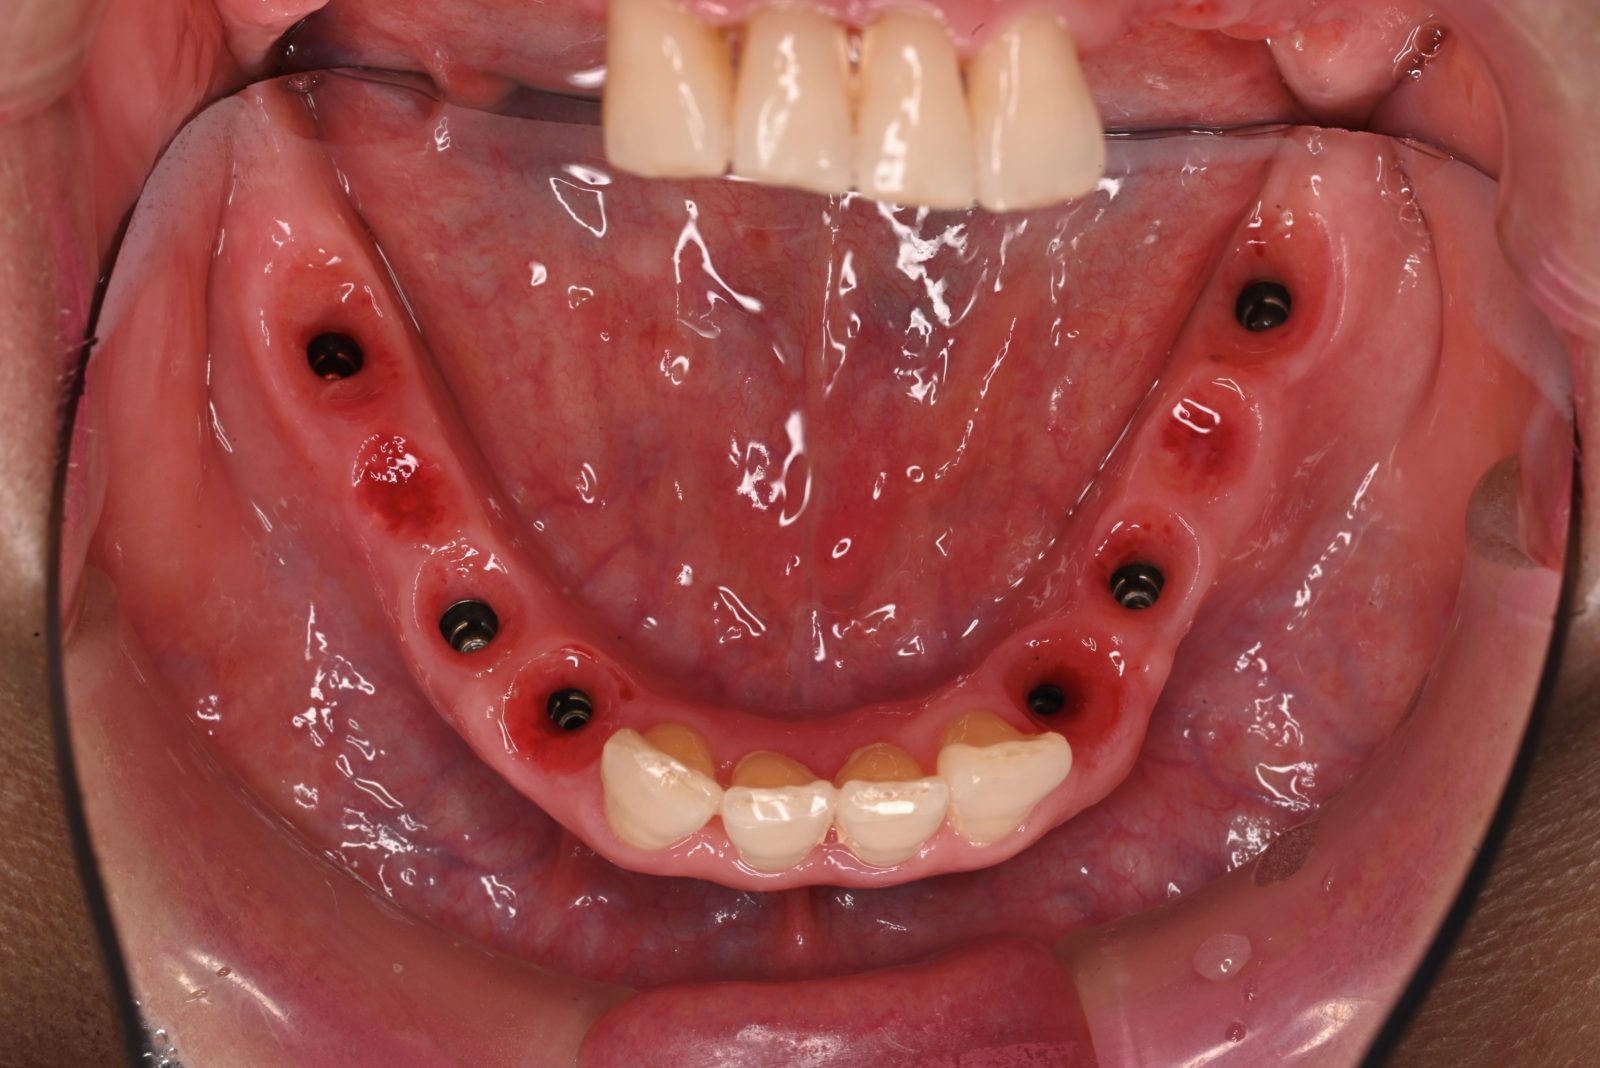

• 治療前

• 治療後